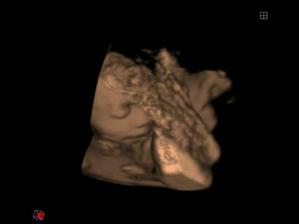

..Matulka se narodil 1.7.08 (36+4), vážil 3,18kg, měřil 50 cm, což nebylo málo 🙂 Pár hodin po porodu se ale vyskytly komplikace, pomalu se mu vstřebávala plodová voda, proto byl umístěn do inkubátoru a napojen na kyslík. Měl potíže i se zažíváním, takže mu byla podávána výživa kapačkami. PO dvou dnech mu začaly sestřičky dávat moje mlíčko stříkačkou a Matulka se začal lepšit. Nicméně zhubnul přes 40 dkg, a byl hodně vyčerpaný. V inkubátoru strávil týden. Po té ho dali do postýlky, ale pořád přespával u sestřiček na novorozenecké JIPce. CHodila jsem za ním každé tři hodky, kdo zažil, ví, kdo nezažil toho děsit nebudu, ale vzpomínky na tuto dobu nemám nejpříjemnější. Další týden jsem si ho pak mohla ´půjčovat´ - vlastní děťátko.. Bylo to nejkrutějších 14 dní v mém životě. Nicméně ted je Matulkovi skoro 8 týdnů a všechno dohnal, v lecčem je dokonce napřed. Je to velmi živé, veselé a věčně hladové miminko 🙂 uf uf .)